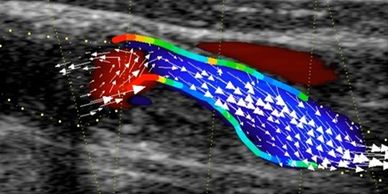

Lasa in urma imaginile Doppler Color, in care directia fluxului sangvin este, simplu, sus-jos! Functia Vector Flow Mapping vizualizeaza dinamica inimii si vaselor, in orice directie, cu vectori de miscare. Acum pot fi vizualizate vortexurile endo-cavitare si se poate analiza formarea lor, dimensiunea si intensitatea. Rezultatul? Date calculate riguros care te ajuta sa detectezi precoce semne suspecte ale afectarii cardiace, ameliorand prognosticul, deciziile de tratament si urmarirea in dinamica pentru monitorizare.

Cele mai multe clinici utilizeaza cateterismul cardiac pentru masuratori ale presiunii intraventriculare stangi. Dar nu ai prefera o procedura non-invaziva? Cu functia VFM se poate calcula, ecografic, gradientul de presiune relativa. Tragi o linie si apesi un buton pentru a obtine diversi indici ai presiunii, de exemplu mmHg. Suctiunea din timpul relaxarii izometrice este prezentata pe o harta color a presiunii, care iti permite sa evaluezi functia diastolica si sa evaluezi rapid riscul insuficientei cardiace.

Turbulenta fluxului cardiac in ventriculul stang poate fi cauzata de stenoza sau complicatii post-interventii chirurgicale. Functia VFM le detecteaza si le caracterizeaza prin evaluarea energiei pierdute: cu cat mai mare pierderea energetica, cu atat mai mare turbulenta. Studiind pierderea energetica - de exemplu la pacienti cu insuficienta aortica, sau monitorizarea inainte si dupa tratamentul valvelor mitrale, s-a dovedit de asemenea utila in intelegerea hemodinamicii.